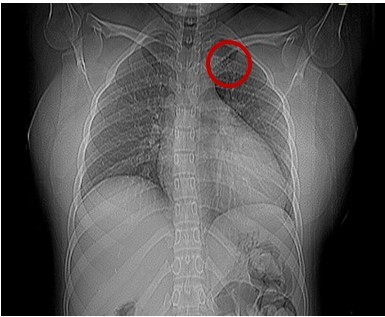

Paciente masculino de 22 años de edad, sin antecedentes patológicos personales ni familiares, quien es referido debido a que un examen radiográfico posteroanterior y lateral, se evidencia como hallazgo incidental imagen radiopaca de apariencia redondeada, de unos 5 cm de diámetro, localizada en el décimo (10o) arco costal posterior izquierdo (Figura7), y por lo cual fue remitido a la consulta externa de la Unidad de Cirugía de Tórax de nuestro centro hospitalario en donde es valorado.

El examen físico practicado se encontró dentro de límites normales, motivo por el cual se ordenan exámenes complementarios de laboratorio e imágenes de TC de tórax con ventana y reconstrucción de pared torácica ósea, asimismo, survey óseo. Exámenes complementarios de laboratorio dentro de parámetro normales.

En la TC de tórax con reconstrucción en 3D, se evidenció imagen hiperdensa con áreas hipodensas en su interior, redondeada de bordes bien definidos microlobulados que mide 4,3 cm x 4,3 cm a nivel del 1/3 proximal del décimo (10o) arco costal posterior izquierdo con protrusión de dicha lesión hacia parénquima pulmonar y partes blandas dorsal compatible con lesión neoplásica benigna. Resto del plano óseo y blando sin evidencia de lesiones (Figura 8).